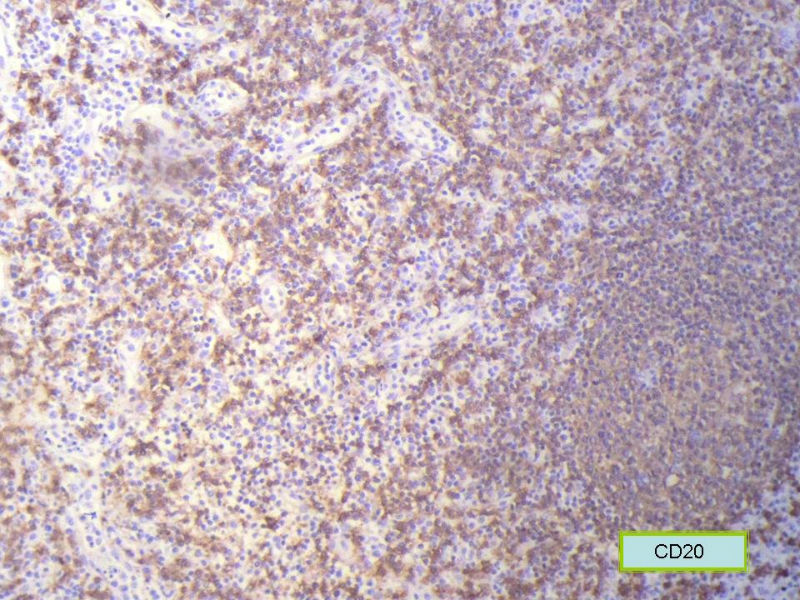

该患者可能存在病毒的感染,抑或是EB病毒的感染,包括CD30+的细胞在内,夹杂在组织细胞、小淋巴细胞之间的一些个大细胞是活化的淋巴细胞,表型看来属B细胞。整个形态呈反应性增生的形态。

标记树突细胞标志物CD21或CD23或D2-40,可能显示树突网与HE见到的明确的滤泡生发中心一致。

Ki-67标记在淋巴滤泡(生发中心)细胞全阳性,而且显示出生发中心边缘规则,不像是肿瘤,呈反应性增生。

Ki-67标记在滤泡间和淋巴组织弥漫增生区见散在阳性细胞,这些阳性细胞可能是转化性淋巴细胞,有的甚至是内皮细胞或组织细胞。

总之,现有的图片显示的形态和IHC标记尚不足以诊断为淋巴瘤,除非有有基因重排的支持。

请看下图,显示的细胞比较杂,胞浆较丰富,胞核没有什么特别的异型性。没有促纤维增生反应和围血管生长表现,没有肿瘤性坏死,没有见到更多的核分裂,特别是病理性核分裂。因此认为,本例是淋巴组织反应性增生,可能是对病毒感染的反应。